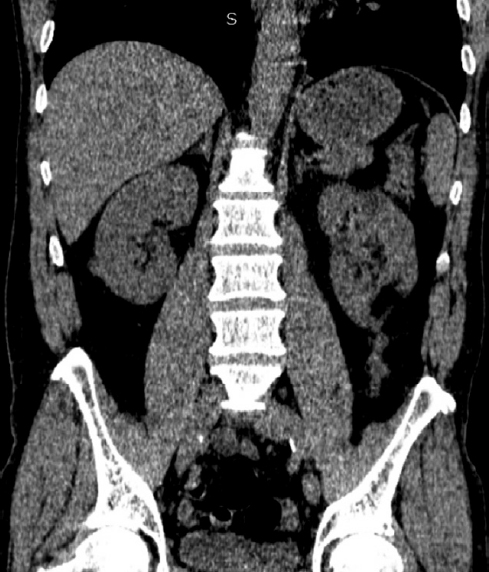

Через 3 мес. после операции пациент приглашен для проведения контрольного обследования. Выполнена КТ мочевыводящих путей с внутривенным контрастированием: почки расположены в типичном месте, в размерах не увеличены, паренхима не истончена, однородная. На границе нижней и средней трети левой почки определяется участок послеоперационных изменений. На месте ранее визуализируемого кистозного образования левой почки определяется дефект кортикального слоя. Чашечно-лоханочная система почек не расширена. Выделительная функция обеих почек своевременная, симметричная. Рентгеноконтрастных конкрементов в проекции мочевыводящих путей не выявлено. При лабораторном обследовании отклонений нет (рис. 6).

Рис. 6. Компьютерная томография мочевыводящих путей с внутривенным контрастированием через 3 мес. после операции.